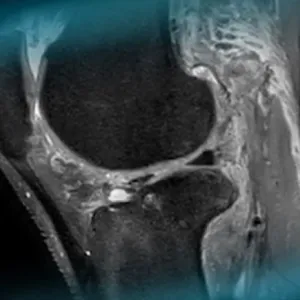

ACL repair is currently a hot topic in knee arthroscopy. Discover the surgical technique proposed by Edoardo Monaco, an Orthopedic surgeon in Rome and a reference for this type of surgery, who performs it with an augmentation with an internal brace.

A 33-year-old male long jump parasport athlete with a transtibial amputated leg suffered an ACL rupture from knee hyperextension, presenting a positive Lachman test and no frontal plane laxity. This case aims to discuss therapeutic options for ACL reconstruction, patient positioning, and graft choice.